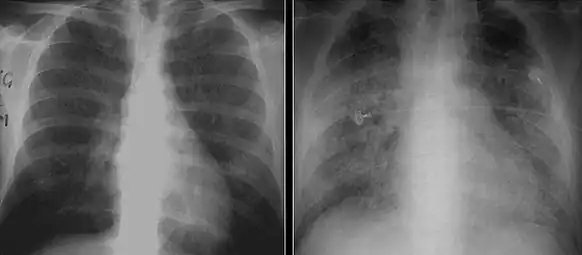

The diagnosis can be confirmed by the characteristic appearance of the chest X-ray and an arterial oxygen level (PaO2) that is strikingly lower than would be expected from symptoms. Gallium 67 scans are also useful in the diagnosis. They are abnormal in about 90% of cases and are often positive before the chest X-ray becomes abnormal. Chest X-ray typically shows widespread pulmonary infiltrates. CT scan may show pulmonary cysts (not to be confused with the cyst-forms of the pathogen).

- Chest X-ray demonstrating bilateral pulmonary infiltrates caused by pneumocystis pneumonia.

- Chest X-ray of increased opacification (whiteness) in the lower lungs.

- These chest radiographs are of two patients. Both show ground glass opacities. The left X-ray shows a much more subtle ground-glass appearance while the right X-ray shows a much more gross ground-glass appearance mimicking pulmonary edema.[6]